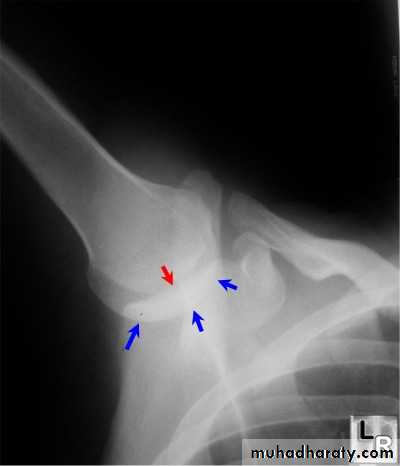

Posterior shoulder dislocation:

* very rare & form about 2-4% of shoulder dislocation.

* Posterior dislocation may be missed initially on frontal radiographs in 50% of cases, as the humeral head appears to be almost normally aligned with the glenoid.

*the internally rotated humeral head takes on a rounded appearance known as the light bulb sign.

*may be associated with posterior glenoid rim or lesser tuberosity.